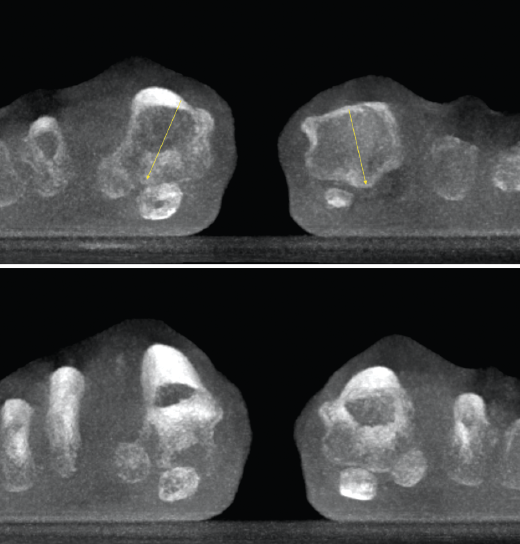

Articulación subtalar

La medición de las caras articulares anterior, media y posterior de la articulación subtalar se complica en un estudio simple radiográfico. La inclinación-orientación de las mismas en relación con la configuración del retropié y su implicación en el medio y antepié han sido estudiadas con la TAC en carga(8).

- Patología y deformidad subtalares. Estudio de la configuración subtalar y artropatía de la misma (Figura 4).